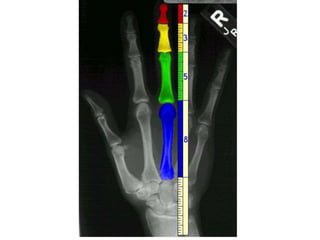

Capul este a 10'a parte din lungimea omului , de la nivelul cotului pana la varful

degetului va fi a5'a parte din lungimea omului , intreaga mana este a 3'a parte din

lungimea omului , palma este a 8'a parte din distantade la nivelul talpii pana la nivelul

umerilor si a 12'a parte din intreaga lungime . Distanta de la mijlocul pieptului pana la

crestetul capului va fi a 6'a parte din lungimea omului . Degetul lung al palmei va fii a

doua parte din intreaga palma , a 8'a parte din intreaga mana si a 24'a parte din intreaga

lungime . Policele va fi a 3'a parte din palma , a 12'a parte din intreaga mana si a 36'a

parte din intreaga lungime . Capul este a 8'a parte din inaltimea omului , de la nivelul

cotului pana la varful degetului va fi a 4'a parte din inaltimea omului si din latimea

omului , latimea capului este a 3'a parte din latimea umerilor , latimea umerilor este a

4'a parte din latimea omului , de la nivelul sanilor pana la nivelul superior al capului va fi

a 4'a parte din inaltimea omului , de la pubis pana la nivelul superior al capului va fi a 2'a

parte din inaltime. Capul va fi egal cu 6 unitati , palma va fi egala cu 5 unitati , talpa va fi

egala cu 7 unitati , distanta de la nivelul umerilor pana la nivelul superior al capului va fi

egala cu 8 unitati , distanta de la nivelul barbiei pana la curbura capului va fi egala cu 4

unitati . Buricul este centrul cercului in care se inscrie omul ,raza cercului va fi egala cu 29

unitati , diametrul cu 58. Patratul care defineste inaltimea va fi egal cu 48 de unitati iar

cel care defineste lungimea va fi egal cu 60 de unitati . Un cubit va fi egal cu 12 unitati .